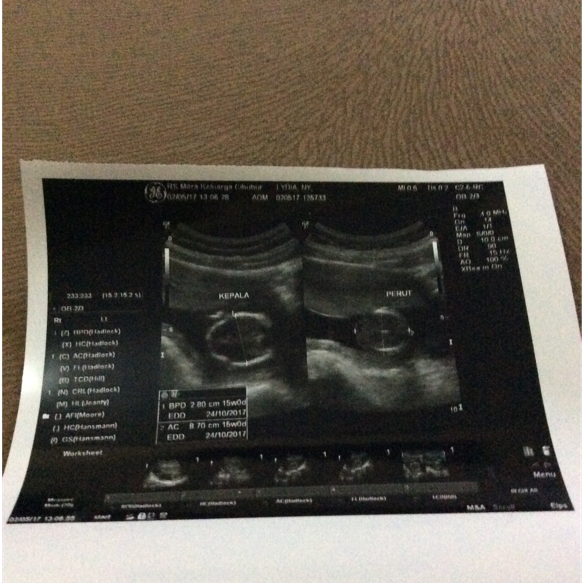

Tadi lumayan agak lama di-USG-nya karena detail, kepala, otak, kaki, tangan, perut, ari-ari, ketuban, tulang punggung. Alhamdulillah semua normal. Tapi organnya belum sempurna, dokternya bilang 19 minggu baru sempurna. Tangannya baru mau misah-misah jarinya.